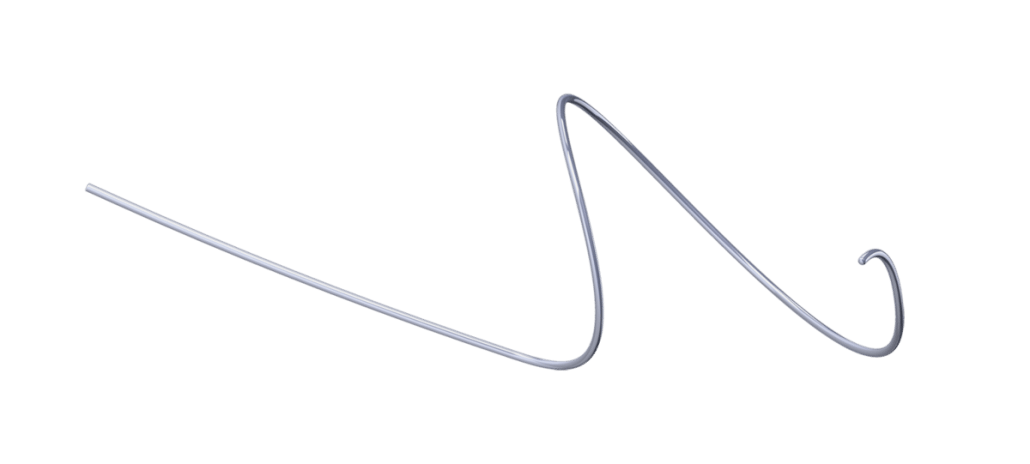

AORTIC ANEURYSM

The aorta runs from the heart through the center of the chest and abdomen. It’s the main blood vessel that brings blood to the abdomen, pelvis, and legs. An abdominal aortic aneurysm (AAA) is a life-threatening condition that occurs when the vessel enlarges, putting it at risk of bursting. Men are 4-15 times more likely to develop an AAA than women

Learn more about AAA. To learn more about our packs, wires, and other cardiac products, please visit our Merit Vascular page.

MERIT PRODUCTS